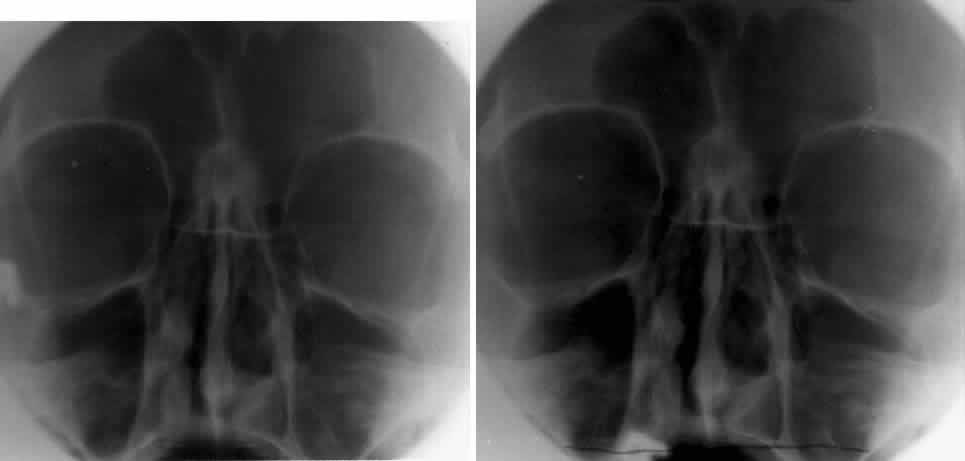

Calcification in the orbit can be seen in retinoblastoma, meningioma, organized hematoma, or a phlebolith associated with venous malformations. Intraocular calcification is seen with tumors such as retinoblastoma or with degenerative changes of the lens, choroid, or vitreous23 (Figs. 10 and 11).

Fig. 10. Caldwell projection of a hemangioma of the left orbit. Soft tissue density is seen in the lateral orbit with partial calcification (arrows).

Fig. 11. A phthisis bulbi globe with calcification of the choroid and sclera. Note the outline of the globe and the location within the orbit. Calcification of the globe can occur with degenerative changes of the eye.